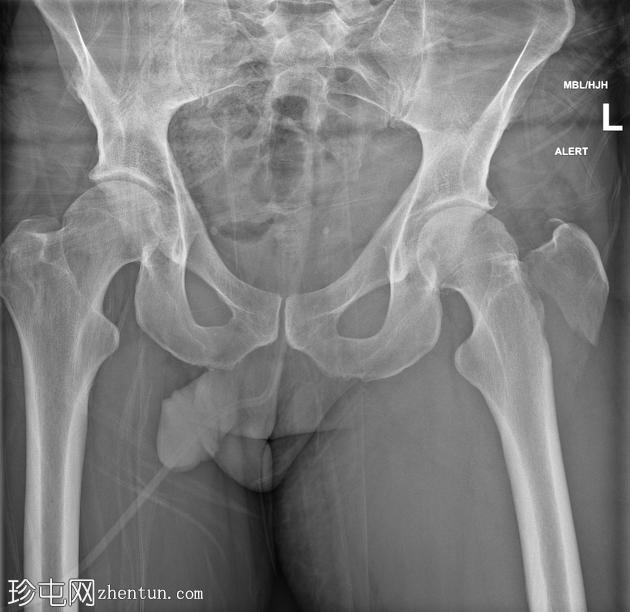

X光片

左侧大转子骨折,侧向移位。髋关节力线正常。

留置导尿管 (IDC)。

非典型骨折,整个大转子骨折,无粉碎性骨折。